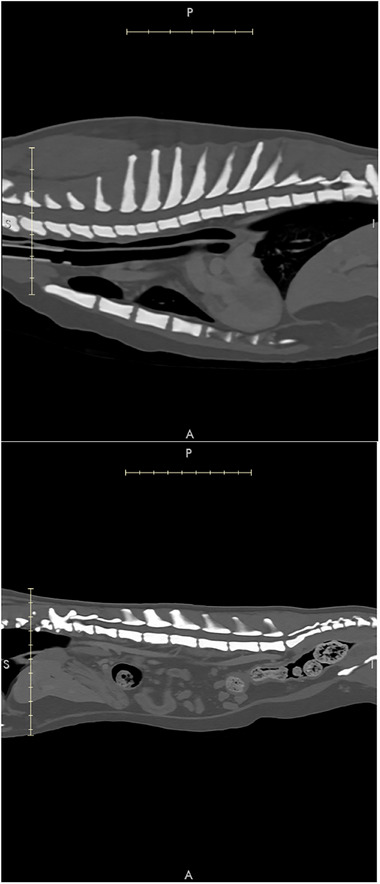

Case summary: A 5-year-old neutered male domestic medium-hair cat was referred to the internal medicine department with upper respiratory signs and limb pain. Computed tomography (CT) revealed diffuse osteosclerosis, showing severe osseous thickening of the nasal turbinates and near-occlusion of the nasal passages. No new or healed fractures were observed. Additional diagnostic tests revealed no infectious or neoplastic causes. The cat was treated supportively for pain and nasal inflammation. One year after the diagnosis, the cat was described as having an acceptable quality of life at home, despite ongoing clinical signs of nasal congestion.

Relevance and novel information: Chronic upper airway congestion is a common presenting complaint in feline patients. This report describes the imaging findings in a cat in which upper airway signs were due in part to systemic bone pathology. Previous reports suggest that the most common causes of chronic nasal congestion are acquired conditions with poor prognosis, such as lymphoplasmacytic rhinitis, neoplasia, or fungal infection. Diseases that cause diffuse osteosclerosis in cats are poorly understood. This report describes a case of diffuse osteosclerosis in a young cat with no other known comorbidities. The clinical picture is similar to descriptions of an osteosclerotic bone disorder in humans commonly referred to as autosomal dominant osteopetrosis type 1. Since no targeted treatments are available to reverse the osseous changes, the patient was treated supportively with pain management and corticosteroids. Recent developments in our understanding and treatment of similar human diseases may guide future advances in veterinary medicine.